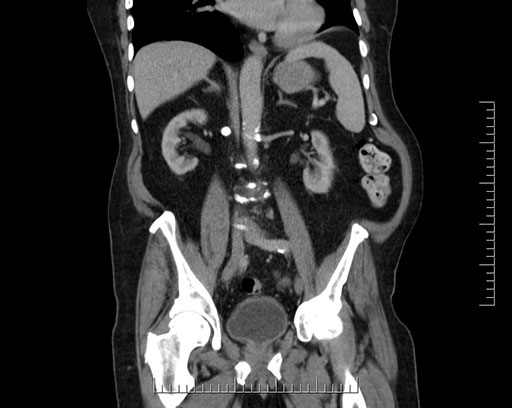

Whipple (pancreaticoduodenectomy) [case 7]

Imaging Analysis

Look through the patient's CT scan to identify any areas of concern for the necessary procedure.

Coronal - stented